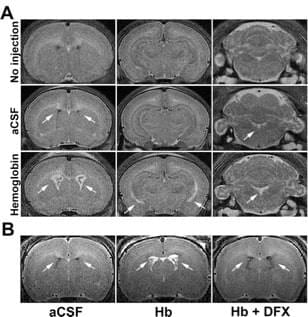

Role of hemoglobin and iron in hydrocephalus after neonatal intraventricular hemorrhage

Neurosurgery. 2014 Dec;75(6):696-705

We reported that intraventricular injections of iron or Hemoglobin(Hb) in P7 neonatal rats resulted in ventriculomegaly, neuronal injury and death. Injection with the iron-deficient immediate heme precursor protoporphyrin IX did not result in ventricular enlargement. Furthermore, treatment with an iron-chelator, deferoxamine, post-Hb injection resulted in significant reduction in Hb-induced hippocampal damage and neuronal injury. These results implicate iron and Hb as key neuropathological substrates of GMH-IVH.This has implications for pathogenesis and treatment of hydrocephalus.

Access full-length article here: https://www.ncbi.nlm.nih.gov/pubmed/25121790

Hemoglobin-induced neuronal degeneration in the hippocampus after neonatal intraventricular hemorrhage

Brain Res. 2016 Mar 15;1635:86-94

We evaluated the role of hemoglobin (Hb) in cell death after intraventricular injection in neonatal rats. Hb was injected into the right lateral ventricle of P7 rats. The CA-1 region of the hippocampus was analyzed via immunohistochemistry, hematoxylin and eosin, Fluoro-Jade C staining, Western blots, and double-labeling stains. Compared to controls, intraventricular injection of Hbdecreased hippocampal volume (27% decrease; p<0.05), induced neuronal loss (31% loss; p<0.01), and increased neuronal degeneration (2.7 fold increase; p<0.01), which were all significantly reduced with the iron chelator, deferoxamine.

Access full-length article here: https://www.ncbi.nlm.nih.gov/pubmed/26772987